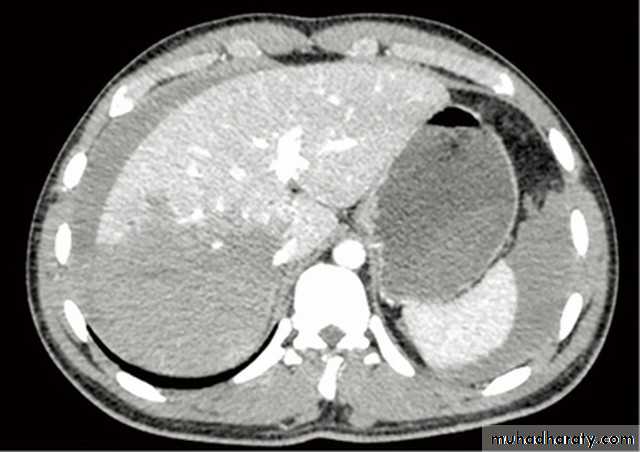

At CT, metastases are seen as rounded areas, usually lower in density than normal liver parenchyma with intense enhancement seen after IV contrast.

At MRI, metastases typically have a signal lower than normal liver on T1 and a high signal intensity on T2.

Primary carcinoma (hepatoma) is usually solitary , but may be multifocal. Its CT,US and MRI features are similar to metastatic neoplasms.